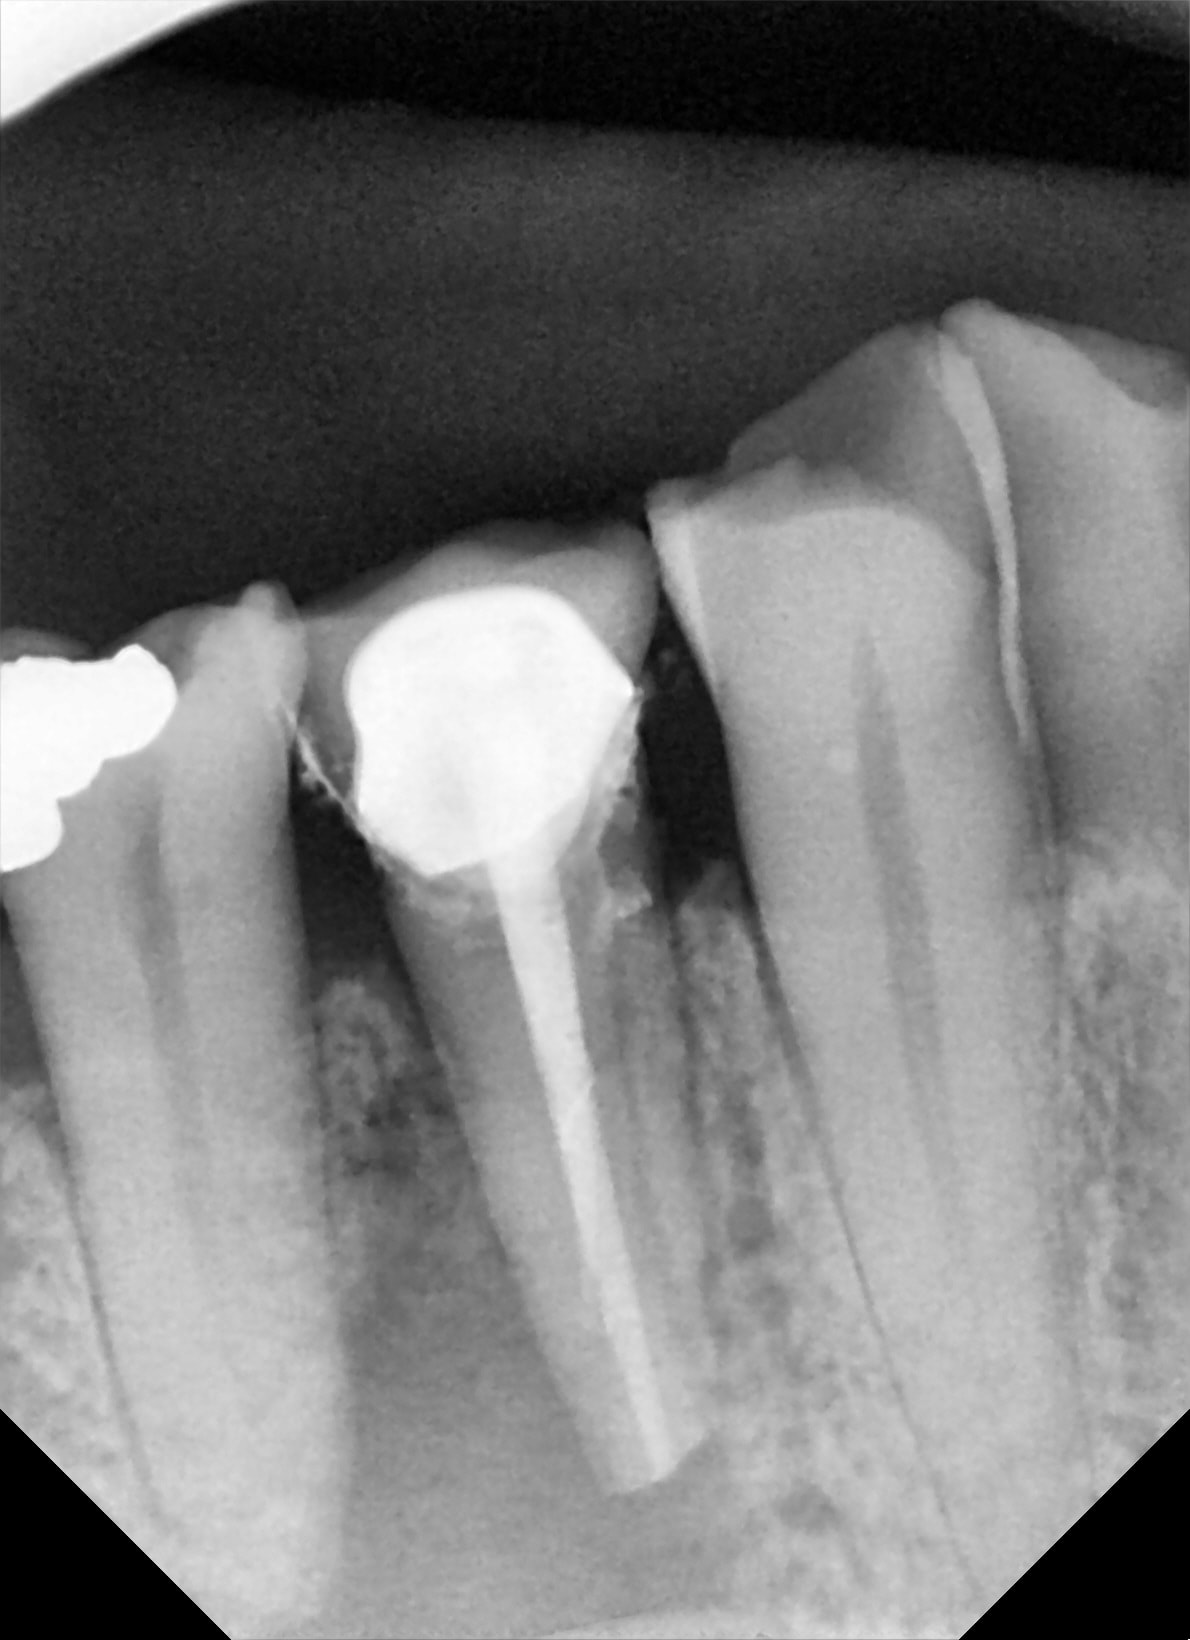

ayé c'est fait !

sous pradaxa ( ou l'autre je sais plus), ça a coulé à flot.

Du coup j'ai coller au superbond.

j'en ai bien chier à l'exo.

La CCM est resté direct dans le davier et vu que je voulais pas bousiller les marges de la préparation, j'ai du y aller molo molo.... long...

sinon j'ai pas eu la foi.. j'ai coupé l'apex

autre retour: j'ai été surpris par la stabilité de la ratoune une fois dans son trou.

J'ai eu le mec au tel, il saigne pas... ouf